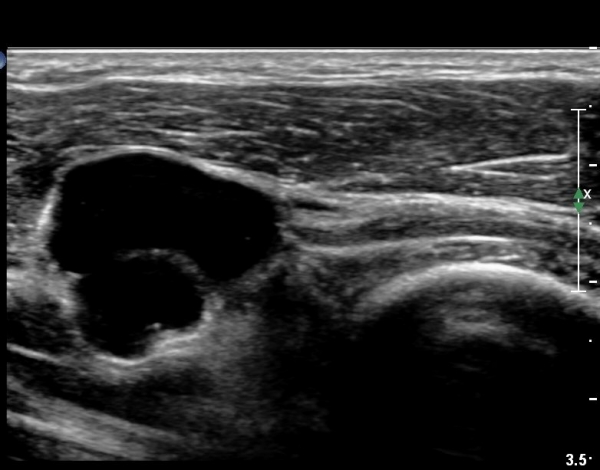

¿ä°ñµÎ ±ÙÀ§ºÎ Ⱦ´Ü¸é°Ë»ç»ó Èİñ°£ ½Å°æ ³»ÃøÀ¸·Î ÀÛÀº ³¶Á¾ÀÌ °üÂûµÈ´Ù(»çÁø 1).